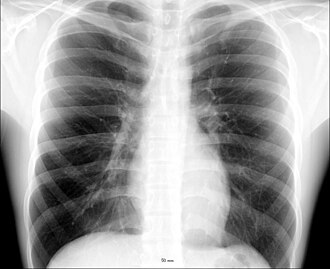

Prsni koš

Prsni koš (lat. thorax) koštano je hrskavični kavez koji sadrži i štiti središnje organe dišnog i krvožilnog sustava. Oblikom je čunjast (uski vrh i široko dno), te dulji straga nego sprijeda. Zbog prodora kralježaka u prsnu šupljinu (cavum thoracis), poprječno pokazuje bubrežasti presijek.